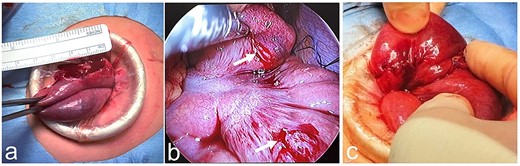

We present our experience with a 6-year-old girl who bruised her abdomen by falling while running with a thermos bottle (water bottle) hanging diagonally across her neck and left shoulder and crossing in front of her body. She went to school with a bruise on her abdomen, but 2 h after the injury she vomited and felt unwell; she was then rushed to the hospital. At the time of examination, her heart rate was 90 beats/min, her blood pressure was 110/62 mm Hg, her respiratory rate was 18 breaths per minute, her oxygen saturation was 98%, and her temperature was 36.6°C. Her abdomen was diffusely tender, but focused assessment with sonography for trauma was negative. She was kept for observation, but her symptoms did not improve. Plain abdominal CT was performed 3 h after the injury and revealed free air in the abdominal cavity, suggesting intestinal injury from blunt trauma. The whole pancreas was checked, but no obvious pancreatic injury was noted. Laboratory assessment showed a white blood cell (WBC) count of 33 200/μL, red blood cell (RBC) count of 4.82 × 106/μL, hemoglobin (Hb) of 13.1 g/dL, hematocrit (Ht) of 40.0%, a platelet count (Plts) of 436 × 103/μL, aspartate transaminase (AST) of 49 IU/L, alanine transaminase (ALT) of 13 IU/L, total bilirubin (T-Bil) of 0.4 mg/dL, and C-reactive protein (CRP) of 0.05 mg/dL (Table 1). She was transferred to our hospital 5 h after the injury. Abdominal examination on admission revealed a bruise and redness at the umbilicus (Fig. 1a), as well as diffuse signs of peritoneal irritation and muscular guarding. Upright chest X-ray showed free air in the right subdiaphragmatic region, but supine abdominal X-ray was normal (Fig. 1b and c). Laboratory assessment was repeated at our hospital and showed a WBC count of 28 960/μL, RBC count of 4.72 × 106/μL, Hb of 13.1 g/dL, Ht of 39.4%, Plts of 384 × 103/μL, AST of 48 IU/L, ALT of 12 IU/L, T-Bil of 0.5 mg/dL, amylase (AMY) of 63 IU/L, and CRP of 0.16 mg/dL (Table 1). Laparoscopic surgery was performed to assess the intestinal injury caused by blunt trauma. A transumbilical vertical incision was made, and the laparoscope was introduced. There were no apparent injuries of the liver and spleen, but there was bile leakage in the right upper quadrant, suggesting injury to the duodenum. However, further examination showed no injury to the duodenum and only the head of the pancreas was observed, but no damage was found. Bloody ascites was observed in the pelvis; biochemical analysis of the ascitic fluid revealed a T-Bil of 1.7 mg/dL and AMY of 6274 IU/L (Table 1). The small intestine was pulled out through the laparoscopic incision to confirm its integrity. There was no apparent injury on the ileocecal side, but there was a perforation on the oral side (Fig. 2a). The perforation was temporarily sewn, and the intestine was returned to the abdominal cavity. The site of injury was determined to be the jejunum, adjacent to the ligament of Treitz and two intestinal serosal injuries were also noticed (Fig. 2b). Two intestinal serosal injuries were repaired, and the perforated portion of the intestine was resected and anastomosed (Fig. 2c). After washing out the abdominal cavity, drains were placed under both hemidiaphragms and in the pelvis. The patient was allowed to begin oral intake on the sixth postoperative day. The drains were removed, blood testing was repeated to confirm return to normal values, and the patient was discharged on the 11th day following an uneventful postoperative course.

Physical and radiologic findings. (a) Abdominal photograph shows a bruise and redness at the umbilicus. (b) Upright chest X-ray shows free air in the right subdiaphragmatic region. (c) Supine abdominal X-ray shows no relevant findings.